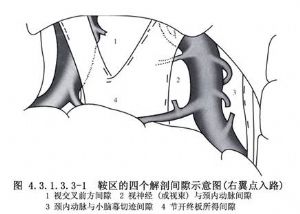

近年來,由於顯微神經外科技術的提高,經翼點入路在顱內腫瘤及動脈瘤手術中的應用日益廣泛。對顱咽管瘤切除術而言,由於這種入路稍加改變就能充分地顯露視交叉前後、視神經-頸內動脈間隙及頸內動脈外側間隙,甚至小腦幕邊緣及頸內動脈分叉部附近的結構,故其適應證較寬。有人(Yasargil,1990)將其用作切除各種顱咽管瘤的主要手術入路(圖4.3.1.3.3-1~4.3.1.3.3-4)。

切開硬腦膜後,首先應貼近額葉開放側裂池,放出腦脊液,牽開額葉和(或)顳葉,顯示同側視神經與頸內動脈。如腫瘤爲腦室旁型或瘤體較大向鞍後擴展,則應於較高處分開外側裂,並打開側裂池根部,以充分顯露頸內動脈分叉部、大腦中動脈與大腦前動脈近端,並開放視交叉前間隙、視神經-頸內動脈間隙與頸內動脈外側間隙,顯露大腦前、中動脈,後交通動脈、脈絡膜前動脈、動眼神經與向鞍旁擴展的瘤體(圖4.3.1.3.3-6)。如腫瘤位於鞍後接近中腦前方,還應切開Lilie-quist膜進入腳間池,必要時還可切開小腦幕遊離緣,打開橋腦前池及環池,顯示向鞍後延伸的瘤體及基底動脈分叉部、大腦後動脈、小腦上動脈、大腦腳和橋腦。